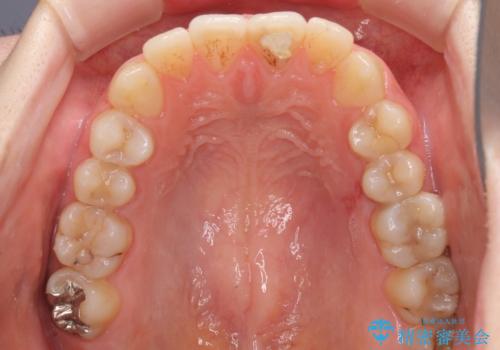

- 口元の膨らみが気になるとのことで来院された患者様です。

非抜歯で口元の突出感を少し改善させる治療も提案しましたが、最大限口元を引っ込めたいとのことでした。

上下左右第一小臼歯4本を抜歯し、ワイヤー装置により矯正治療を行うこととしました。